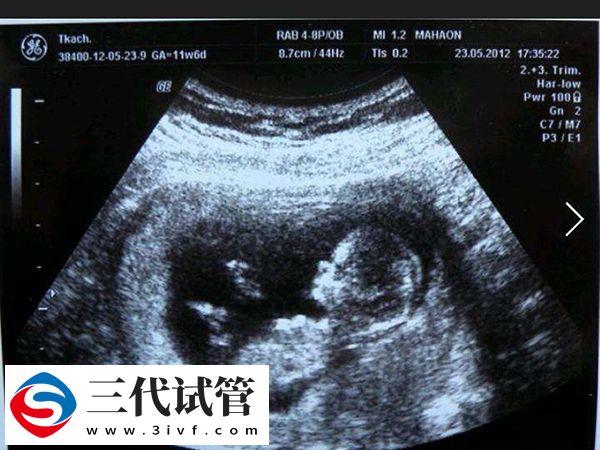

即使进行了三代PGS(胚胎植入前遗传筛查),仍然建议进行NT检查。NT检查通过超声波测量胚胎颈部区域内液体积累的厚度来评估胎儿是否存在染色体异常或心脏畸形等风险,通常在怀孕11到14周之间进行这项检查是比较理想的时间窗口。以下是主要原因: